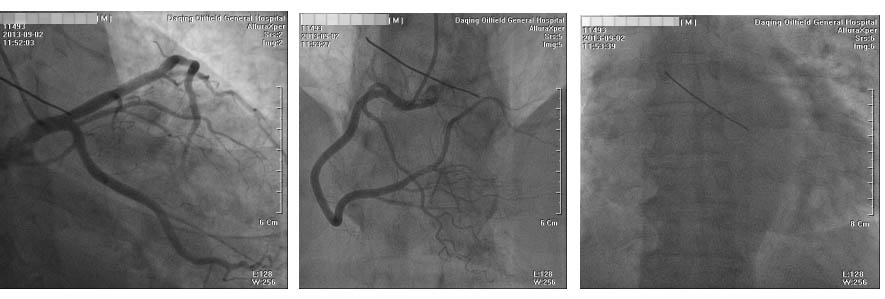

1 资料与方法患者男性,56岁。因间断活动后胸闷痛10余天入院。既往否认高血压、糖尿病,有长期吸烟史。患者近10余天于快速行走及劳累时出现心前区闷痛,无放散痛,无晕厥,休息后胸痛可自行缓解,近2天活动时胸痛频繁发作,且胸痛程度加重。本院门诊行超声心动图示左房38 mm,EF值66%,左室饱满,左室壁增厚,升主动脉稍宽,左室松弛性下降,门诊以“冠心病”收入院。入院查体:T 36.2 ℃,血压 159/84 mmHg(1 mmHg=0.133 kPa),一般状态尚可,呼吸平稳,口唇无发绀,胸壁皮肤无损伤,双肺未闻及啰音。心率62次/min,律齐,未闻及杂音。心电图示心率78 次/min,RV5>2.5 mV,心肌肥厚劳损;急诊肌钙蛋白I测定正常;急诊心肌酶CK-MB正常。入院初步诊断:急性冠脉综合征。入院第3天行冠脉造影示左右冠脉血管未见狭窄病变,透视下可见心包前壁一长约40 mm疑似金属条样物(图 1)。后行胸部CT血管三维成像见升主动脉前方可见条形高密度影,周围可见放射状伪影,长约5 cm,病变自右上至左下走行,于主动脉根部同右心室璧界限不清(图 2)。诊断:心脏异物。停用所有抗血栓药物,并转入我院胸外科治疗,转入胸外科1周后,在全麻下行“心脏异物清除术”,术中于主动脉根部前间壁、右冠开口旁2 cm,可见一长约0.5 cm金属条索样异物,通过主肺动脉窗刺入右心室流出道前壁心肌内,心表面无震颤,围绕异物刺入点,用4-0 prolene 线加垫片荷包缝合两圈,缓慢拔出金属异物,金属异物在心肌内长度约5.5 cm,测量金属条索样异物长度约6.0 cm,刺入点无出血,结扎荷包线(图 3)。术后诊断:心脏异物(金属丝)。追问病史,患者业余爱好舞鞭,该铁丝正是入院前10余天舞鞭时丢失的鞭子头端铁丝(鞭子梢)。术后手术切口愈合良好,术后第6天办理出院。

| 图 1 患者冠脉造影及胸部透视结果 |